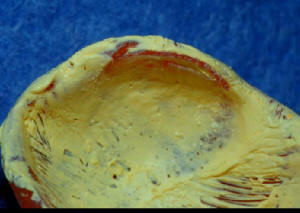

- En la imagen derecha inferior se observan las superficies de

sobrepresión, que deben ser aliviadas con fresa adecuada

- Se realiza el alivio con fresa, el desgaste debe ser

superficial, para no desgastar demasiado. Ver imagen inferior

| Zona de sobrepresión que muestra el color

rosa del acrílico |

Estos problemas pueden ser

solucionados durante la consulta dental, dado que solo requiere la

eliminación del problema con instrumental rotatorio y el posterior pulido

con pómez y cepillo. |